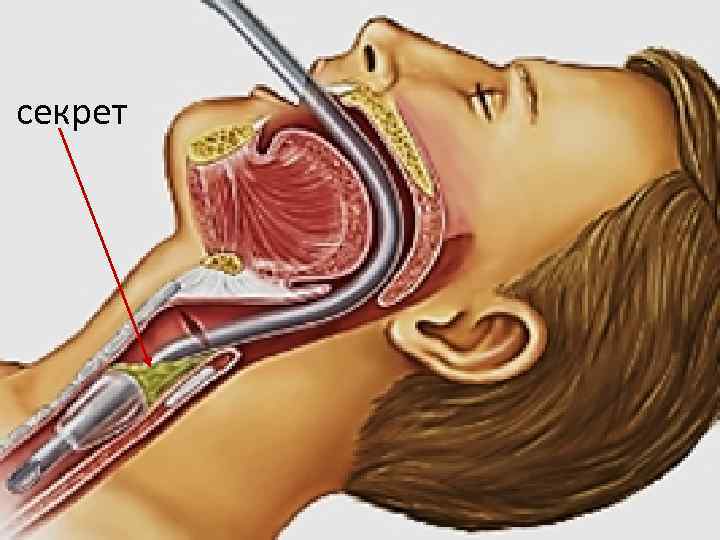

секрет

секрет

Санация надманжеточного пространства Muscedere J, et al. Crit Care Med 2011

Санация надманжеточного пространства Muscedere J, et al. Crit Care Med 2011